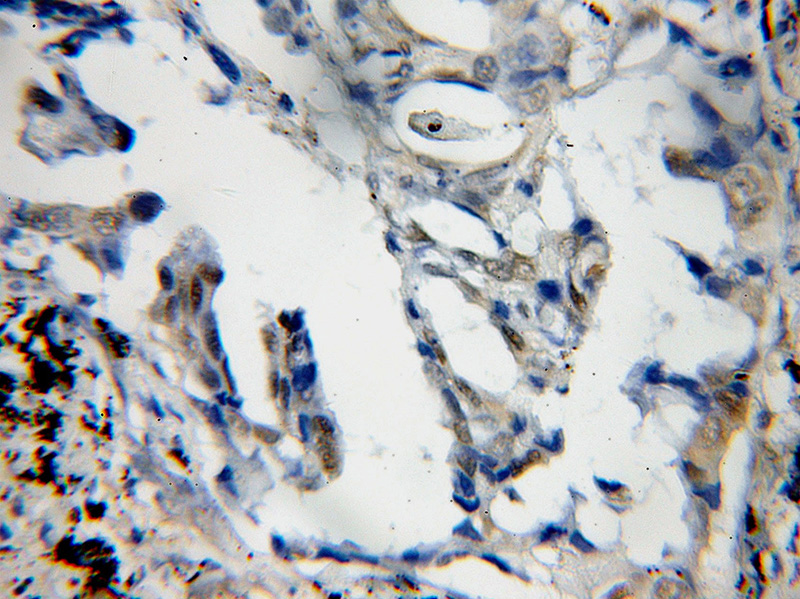

Immunohistochemical of paraffin-embedded human lung cancer using Catalog No:110458(FAM107A antibody) at dilution of 1:50 (under 10x lens)